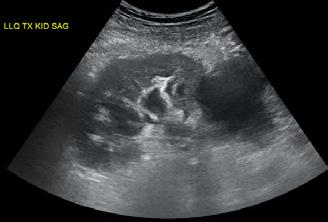

A opera sau a nu opera? Raspunsul ecografistului

Dr. Dan Adrian Stănescu 24